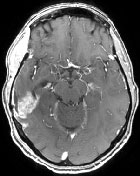

Cas clinique n°1. Chimiothérapie in situ en 1ère ligne avec protocole Stupp. Patient de 58 ans, droitier, KPS 100. Crise d’épilepsie partielle motrice inaugurale. Découverte d’une lésion nécrotique fronto-centrale droite...